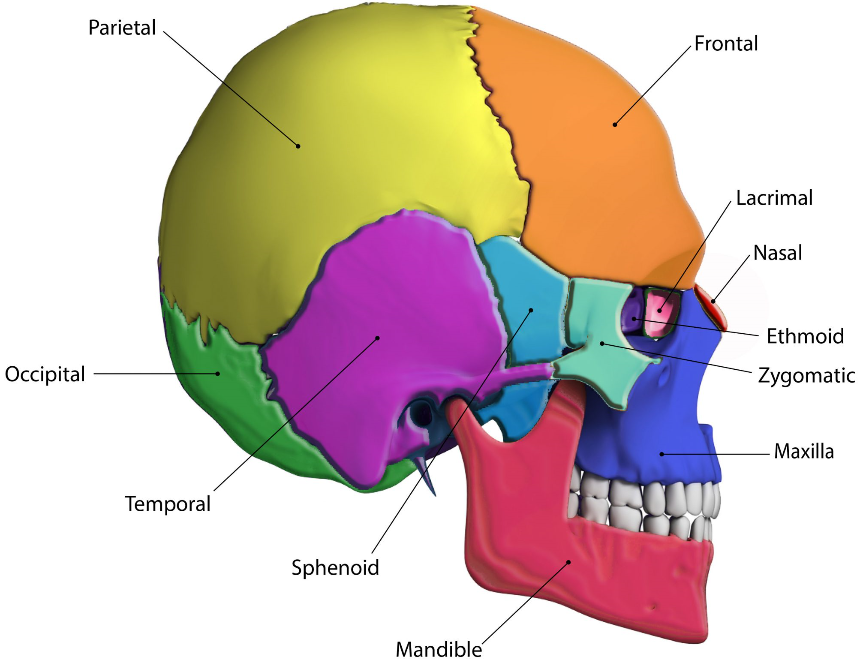

What are the bones that make up the skull and facial skeleton?

Skull (8):

Facial skeleton (15):

Label this.